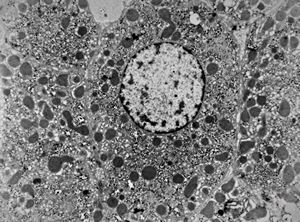

M,66y. | siderosomes

M,66y. | hemosiderin - siderosomes